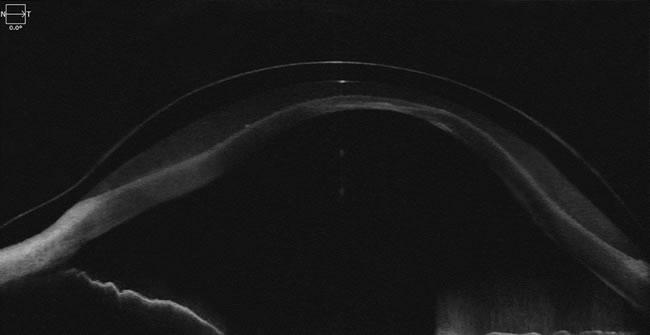

AS-OCT Image of Gaudi lens on the eye. Courtesy of Dr. Aaron Wolf, Austin Optometry Group.

However, when using OCT for evaluating scleral lens thickness and vault, one must be careful. Many specialty contact lens fitters who routinely use OCT for evaluating corneal clearance will tell you that OCT measurements often overestimate the scleral lens vault. We recently encountered a similar effect, when the lens that was manufactured with a 300-µm central thickness was measured by an OCT to be 417-µm.